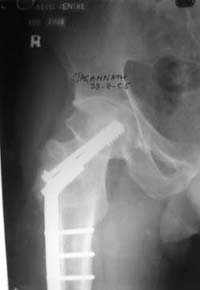

При явно выраженном варусе и флексионных состояниях после сросшихся переломов шейки бедра у молодых рекомендуется реконструктивная операция по исправлению варуса для предотвращения раннего деформирующего артроза, приводящего в результате переднего импинжмента, как показано на снимке.

Межвертельная вальгусная остеотомия представляет наименьший риск среди всех реконструктивных операции в проксимальной части бедра, создавая наилучшие биомеханические условия (увеличивается сила абдукторов, увеличивается сила суставной реакции, уменьшение рычага моментов абдукторов и уменьшение скольжения) и при меньшем риске повреждения кровоснабжения головки, где обычно в 90% случаях достигается отличный результат при применении метода для лечения ложных суставов шейки бедра.

После вальгусных межвертельных операции уже через 2 месяца можно получить результат (predicted outcome), а когда после спонгиозных шурупов результат надо ждать не менее 3-4 месецев, а иногда при свежих переломах сращение в шейке бедра наступает не раньше 5-6 месяцев, тем более при таком варусе спонгиозная фиксация не гарантирует дальнейшее скольжение перелома и ухудшения варуса.

По моему, 120 градусная угловая пластина blade plate решит все проблемы, только необходим предварительный расчет угла остеотомии, и во время фиксации пластины не забыть латерализацию бедра, иначе ось конечности от варуса перейдёт в нежелательный вальгус.

Для предупреждения вальгуса клинок пластины берется на 10-12 мм длиннее чем предварительный туннель на головке, тогда во время

фиксации за бедро пластина автоматически приблизит бедро и происходит латерализация бедра. Если между клинком и латеральным кортексом бедра положить частицу кости от остеотомии тогда образуется дополнительная компрессия на фокусе несращения.

Здесь мои диаграммы для расчета угла остеотомии и латеризации бедра.

the best option is valgus osteotomy with DHS and also additional canceelous screw fixation. the idea is to convert vertical shear foeces to horriszontal

compressive force

Остеотомия, описанная Marti (1989), и о которой нам напоминает Джолдас, как раз хороша тем, что не создает проблем при эндопротезировании.

Это, наверно, относится к медиализирующим остеотомиям при коксартрозе. У обсуждаемой операции как раз результаты хорошие у 80%.